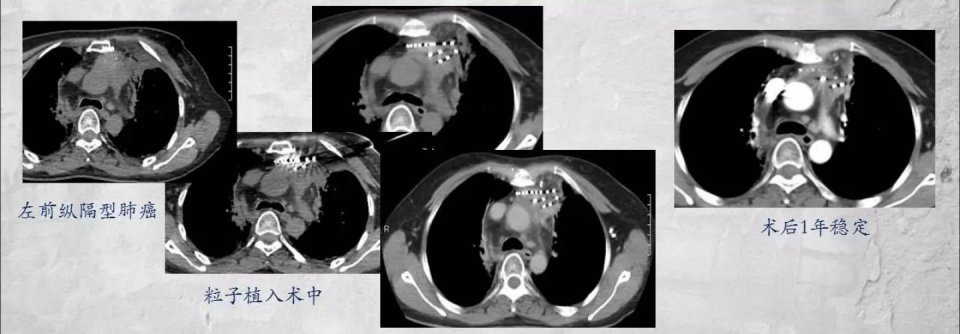

如下图这位42岁的女士,左侧纵隔型肺癌,没有手术条件,采用放射性粒子植入治疗,术后1年病情稳定。